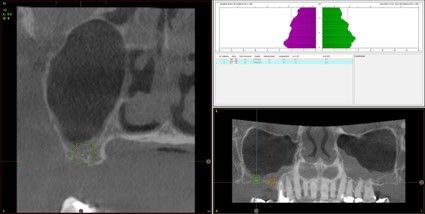

Resultados. Fueron reclutados 13 pacientes en los que se insertaron 30 implantes. Una vez insertados y cargados los implantes, la altura media final fue de 9,68 mm (+/- 2,66), lo que supone una ganancia promedio de 5 mm. A los 10 años, se observó una disminución media de la altura ósea ganada en los implantes en conjunto de 0, 29 mm (+/- 0,77). La media de la pérdida ósea mesial fue de 0,73 mm (+/- 0,75 mm) y la media de la pérdida ósea distal fue de 0,98 mm (+/- 1,2 mm). La supervivencia fue del 100%.

Results.Thirteen patients were recruited and 30 implants were inserted. Once the implants were inserted and loaded, the mean final height was 9.68 mm (+/- 2.66), which represents an average gain of 5 mm. At 10 years, there was a mean decrease in the overall bone height gain of the implants of 0.29 mm (+/- 0.77). The mean mesial bone loss was 0.73 mm (+/- 0.75 mm) and the mean distal bone loss was 0.98 mm (+/- 1.2 mm). Survival was 100%.

Nuestro grupo de estudio modifica esta técnica de elevación transcrestal utilizando para el acceso unas fresas de corte frontal que permiten eliminar la cortical inferior del seno con lentitud sin dañar la membrana de Schneider, eliminándose los osteotomos y el malestar que genera su accionamiento mediante el martillo6-7. Inicialmente el procedimiento fue concebido para ser empleado con material de injerto al igual que el abordaje convencional, pero posteriormente se presentaron variaciones del procedimiento donde se insertaban los implantes sin injerto, utilizándose el propio implante como mantenedor de espacio entre la membrana de Schneider y la cavidad creada entre la membrana y la cresta, permitiendo que esta cavidad no se colapsase y posteriormente fuera colonizada por nuevo hueso7-11.

Los senos tratados con la técnica de elevación transcrestal sin material de relleno muestran un incremento de entre 2,5 mm12,13 hasta 4.4 mm14,15 en la altura ósea lograda sobre el ápice y una supervivencia de los implantes que se sitúa entre un 94 y un 100%16-17. En este trabajo se presenta un estudio retrospectivo donde se ha evaluado la inserción de implantes extracortos (5,5 y 6,5 mm) en zonas posteriores maxilares mediante la técnica de elevación de seno transcrestal con la fresa de ataque frontal sin la utilización de material de injerto, con un tiempo de seguimiento de 10 años para poder objetivar el comportamiento de los implantes a largo plazo y de la técnica empleada.